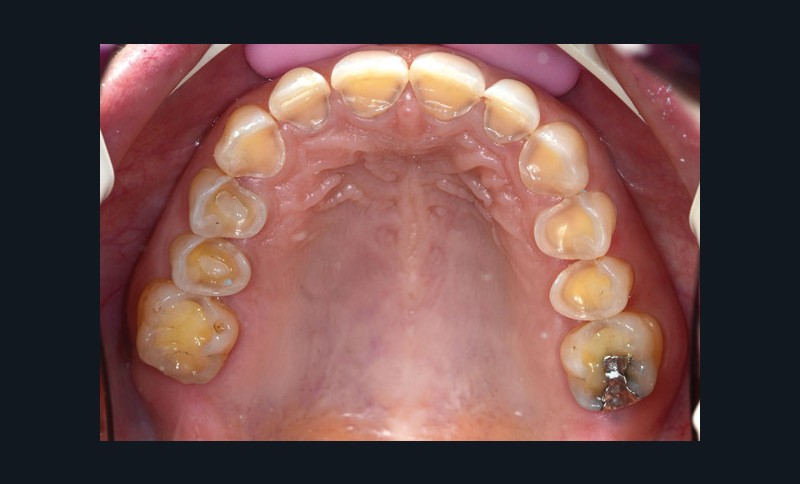

À l’examen clinique (fig. 2 à 4), on observe :

– l’absence de 17, 27 et 47 (suite de lésions carieuses volumineuses) ;

– un parodonte sain ;

– des érosions sévères généralisées, symétriques et bilatérales (occlusales, palatines et vestibulaires au maxillaire) ;

– des lésions carieuses débutantes de site 3 ;

– des obturations préexistantes infiltrées ;

– une vitalité pulpaire conservée sauf au niveau des prémolaires maxillaires ;

– une usure des bords libres des incisives mandibulaires